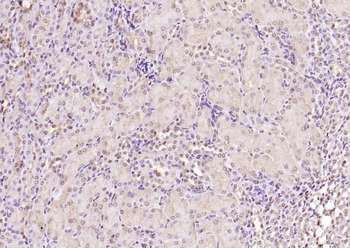

100 μl, 50 μl, 200 μl - ATF4 Recombinant Rabbit Monoclonal Antibody [orb704304]Featured

FC, ICC, IF, IHC-Fr, IHC-P, WB

Human

Mouse

Rabbit

Recombinant

Unconjugated

50 μl, 100 μl - MARK3 Recombinant Rabbit Monoclonal Antibody [orb704310]Featured